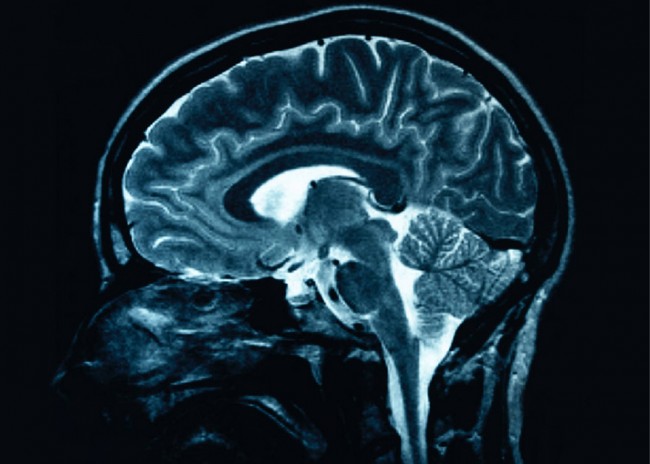

O’Keefe originally used rats and studied their hippocampus when placing them in different parts of the room. In his theory it was these types of brain cells that helped them form a map of the room so that they could navigate, no matter which part of the room he placed them in. The Mosers named these parts “grid cells,” though they studied another part of the rats’ brains called the entorhinal cortex.

This research, along with years of research from other Nobel prize winners, could help determine exactly how Alzheimer’s takes over the brain and maybe even help scientists determine a way to cure the disease. Now that they have the information on how spatial cells in the brain represent memory, John O’Keefe plans to take his research even further. He is now the director of a new brain institute in the city of London. He plans to find a way to attach Alzheimer’s disease at a molecular level and with the new high-tech equipment that he will have for the studies, along with prize money that he has been given, he may be able to do just that.